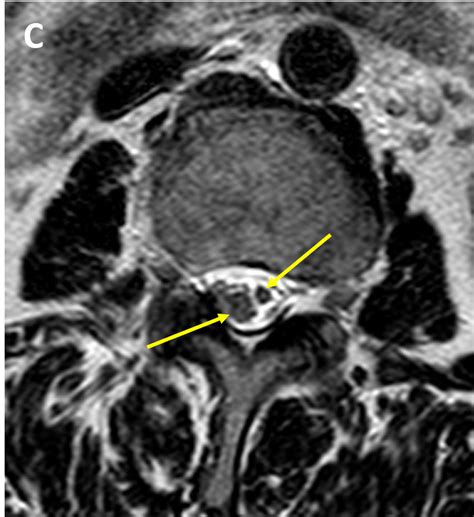

Tethered Cord MRI plays a pivotal role in the diagnosis of tethered cord syndrome. This imaging technique uses magnetic fields and radio waves to produce detailed images of the spinal cord and surrounding structures. Unlike traditional MRI, Tethered Cord MRI focuses specifically on the spinal cord, providing high-resolution images that can detect even the slightest abnormalities.

One of the key advantages of Tethered Cord MRI is its ability to visualize the spinal cord in multiple planes. This allows radiologists to get a comprehensive view of the spinal cord and identify any areas where it may be tethered. The images obtained from Tethered Cord MRI are also highly detailed, making it easier to pinpoint the exact location and extent of the tethering.

After the Tethered Cord MRI procedure, the images will be reviewed by a radiologist who specializes in interpreting MRI scans. The radiologist will look for signs of tethered cord syndrome, such as:

• Abnormal Attachments: The spinal cord may be attached to surrounding tissues, such as the dura mater or vertebrae, in an abnormal manner.

• Thickened Filum Terminale: The filum terminale is a thin, fibrous structure that anchors the spinal cord. In tethered cord syndrome, this structure may be thickened or shortened.

• Spinal Cord Stretching: The spinal cord may appear stretched or elongated, indicating that it is being pulled down by the tethering.